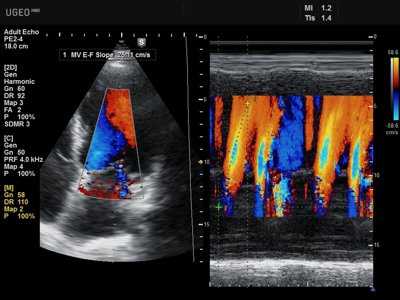

Во время эхокардиоскопии доктор использует различные режимы УЗ аппарата:

- цветового допплера - ЦДК (для определения направления потоков крови и выявления патологических),

Цветовой допплер (Color Doppler). Цветовой допплер - аналог импульсного допплера, где направление и скорость кровотока картируется различным цветом. Так кровоток к датчику принято картировать красным цветом, от датчика - синим цветом. Турбулентный кровоток картируется сине-зелено-желтым цветом.